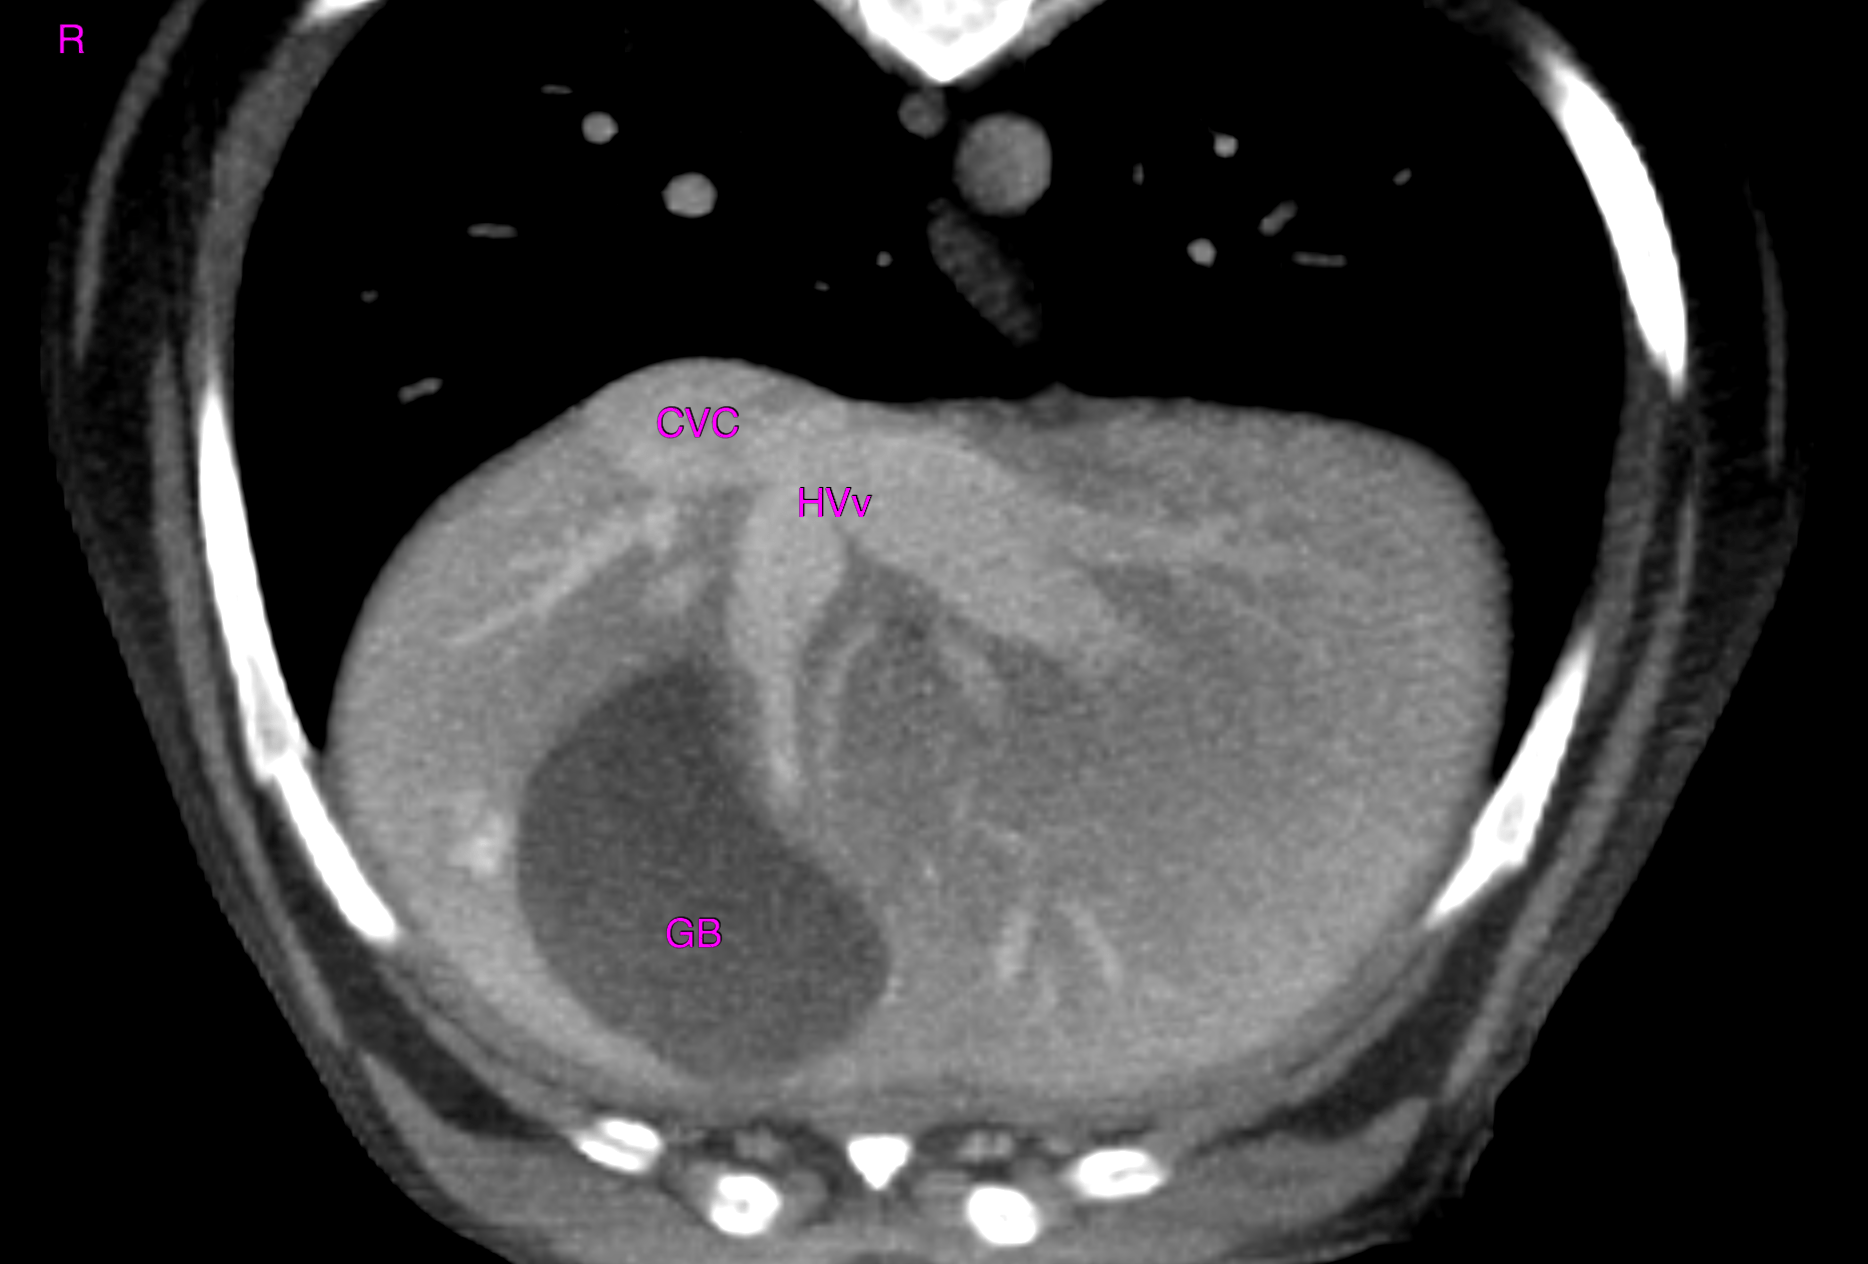

CT – Structurally normal abdomen in a 10 year old MN Dachshund with history of elevated liver enzymes

This 10 year old Dachshund has a history of liver enzyme elevation of at least 6 months duration.

CT of the abdomen – The computed tomographic findings of the liver and remainder of the abdomen are within normal limits.

No evidence of structural pathology within the abdomen